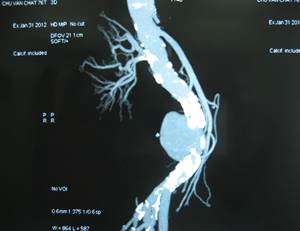

4.5.1.Kết quả:27 BN được mổ có 19 BN mổ cấp cứu và 8 BN mổ có kế hoạch. Có 9 BN khối phồng đã vỡ trong đó vỡ ra sau phúc mạc chiếm đa số, 1 BN vỡ vào ổ bụng và 3 BN vỡ vào cột sống thắt lưng. Kết quả này cao hơn hẳn so với nghiên cứu của các tác giả nước ngoài, AbdelAzim.T.A (20%) [1], Muller (24%)[8], nguyên nhân có thể do thực tế người Việt Nam chỉ đến bệnh viện khi bệnh đã nặng.

Hình 3: Phình động mạch chủ bụng vỡ vào cột sống thắt lưng và thay động mạch nhân tạo hình chữ Y

Một BN PĐMCB vỡ vào cột sống thắt lưng sau mổ 48h xuất hiện đau bụng dữ dội và sốc, được mổ lại cấp cứu phát hiện hoại tử toàn bộ hỗng tràng, hồi tràng và đại tràng mặc dù đoạn mạch nhân tạo thông tốt. Chúng tôi nghĩ đến tắc động mạch mạc treo do lóc ĐMCB vì động tác kẹp clamp. Một BN PĐMCB đã vỡ vào khoang sau phúc mạc có tiền sử suy thận độ IV, 10 ngày sau mổ xuất hiện dấu hiệu nhiễm trùng, đau bụng và suy thận nặng lên. Mổ lại phát hiện khối apxe sau phúc mạc quanh mạch nhân tạo, mạch vẫn thông, không bục. Dù đã làm sạch, dẫn lưu apxe, tình trạng nhiễm trùng không cải thiện (có thể do liệu pháp kháng sinh sau mổ ở BN này không có hiệu quả). Cả hai BN mổ lại đều tử vong. So sánh với một số tác giả nước ngoài, trong nghiên cứu của Muller [8]tỷ lệ tử vong tại bệnh viện 36% (12/33BN). Szeberin Z [9] thay mạch nhân tạo tráng bạc cho 42 BN, biến chứng tắc mạch sớm là 8 BN, muộn là 2 BN, 8 BN phải cắt cụt sau mổ, tỷ lệ tử vong sớm 3 BN (8%), muộn 11 BN (38%). Theo Batt tỷ lệ tử vong quanh thời điểm phẫu thuật và trong phẫu thuật là 46% và 21%[7].